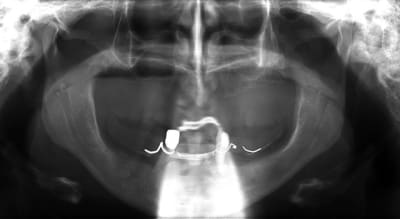

15/05/2009 à 15h07

voili, voila...

avant de faire la tomosynthèse je comprenais pas pourquoi j'avais aussi peu de contraste.

le patient ne souhaite pas, ou ne peut pas se faire poser 6 implants en haut, donc...overdenture sur 4. (si possible)

4 mini implants de prévues en bas...

ok , en voilà...

ceux sont les photos du guide radio.

Mon prothésiste est un petit rigolo qui s'amuse à colorer les dents.

Ici le guide radio est préparé pour laisser passer l'embout de calage lors de la tomosynthèse de façon à ce que les deux appareils soient parfaitement stables.

les deux incisives centrales sont donc meulées.